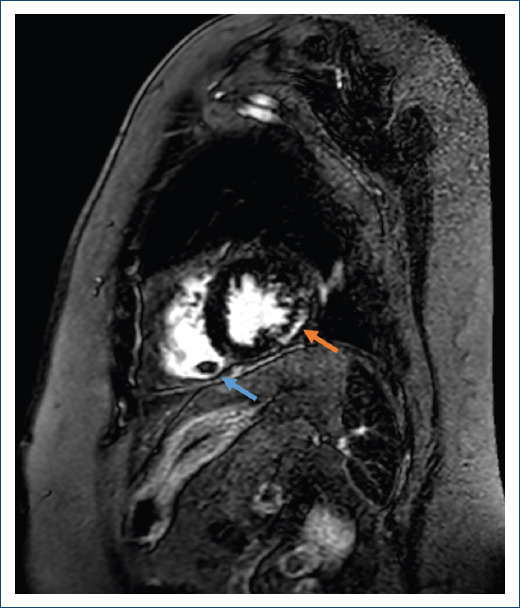

A 74-year-old woman without previous medical history except for the left bundle branch block was admitted for evaluation of recurrent syncopes. During admission, she experienced a sustained self-limited monomorphic ventricular tachycardia together with new syncope. Initial echocardiography displayed moderate biventricular systolic dysfunction. Cardiac magnetic resonance imaging (CMRI) confirmed these findings (Fig. 1) and revealed patchy subepicardial areas of late gadolinium enhancement within the left ventricular inferolateral and apical segments (red arrow) and an aneurysm was found in the right ventricular apex, containing a rounded thrombus (blue arrow) which persisted 10 days after intravenous anticoagulation therapy.

Figure 1 CMRI. Short axis. Inversion-recovery sequence. Late gadolinium enhancement in inferolateral wall (red arrow). Aneurysm in the right ventricle containing a rounded thrombus (blue arrow).